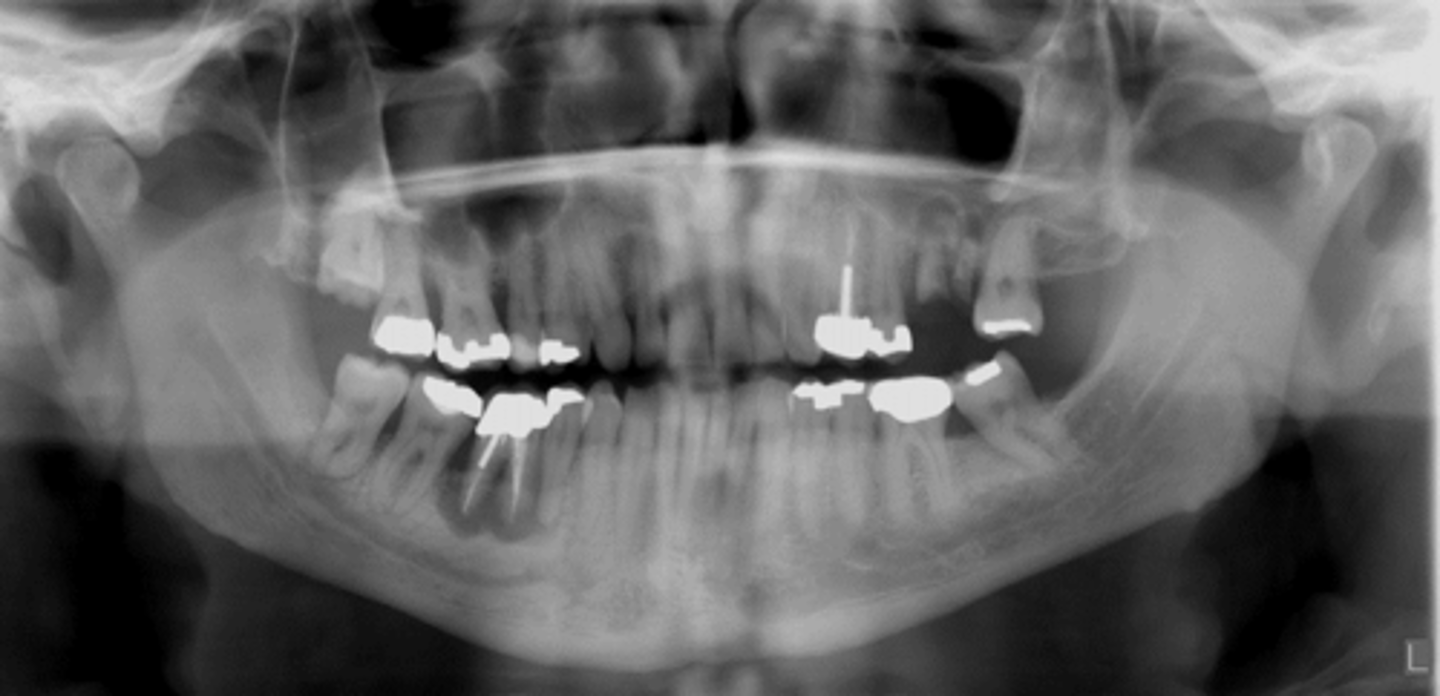

What is osteomyelitis due to?

Hypovascularity

What do you feel during acute osteomyelitis?

Pain

Is there radiograph manifestation during the acute phase of osteomyelitis?

No

Which gender is more affected by osteomyelitis in the mandible?

Men

What indicates osteomyelitis if borders are irregular?

Choose osteomyelitis

What is sequestration in chronic osteomyelitis?

Necrotic bony islands

What develops during chronic osteomyelitis?

Sinus tract